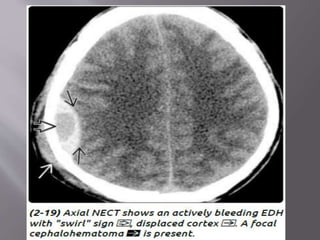

 CT - classic (arterial) EDHs is a hyperdense (60-

90 HU) biconvex extraaxial collection (2-18).

Presence of a hypodense component ("swirl"

sign) is seen in about one-third of cases and

indicates active, rapid bleeding with

unretracted clot.

“Buckling" the gray-white matter interface

 Imaging findings associated with adverse clinical

outcome are thickness > 1.5 cm, volume > 30 mL,

pterional (lateral aspect of the middle cranial fossa)

location, midline shift > 5 mm, and presence of a

"swirl sign" within the hematoma on imaging.